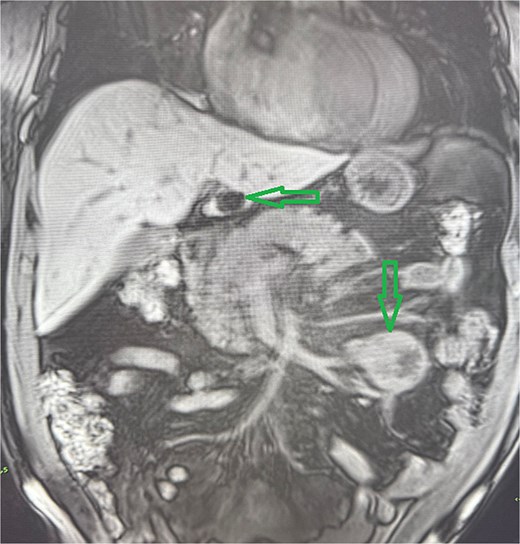

A 53-year-old obese polymorbid patient was initially examined by his general practitioner for 2 months of fatigue. Routine blood tests, physical examination, and X-rays of the lungs were unremarkable. Abdominal ultrasound examination diagnosed resistance in the left mesogastrium and no other pathology was found. The patient was referred to the surgical department for further examination. Abdominal examination was supplemented with computed tomography (CT), which diagnosed a circumscribed hypodense mass of 52 mm at the root of the mesentery in the left mesogastrium and suspected solitary metastatic liver disease (Fig. 1). Massive lymphadenopathy was considered in the differential diagnosis of mesenteric root resistance. Magnetic resonance imaging (MRI) was also indicated to verify the CT findings. MRI examination of the abdomen showed a tumor resistance of 58 × 45 × 45 mm in the root of the mesentery in the left mesogastrium and metastatic liver damage, including lymphadenopathy in the mesentery, was also excluded. The liver mass was diagnosed as a cyst (Fig. 2). According to MRI examination, a possible gastrointestinal stromal tumor, neurogenic tumor, or solitary fibrous tumor was considered as part of the differential diagnosis of mesenteric root resistance. The examination of oncological markers was negative. To investigate the etiology of resistance in the root of the mesentery, a biopsy of resistance was performed under CT control. The biopsy examination showed an ancient schwannoma with positive protein S100 and SOX10 on immunohistochemical examination. Based on the decision of the interdisciplinary indication seminar, the patient was indicated for elective surgery, laparoscopically assisted ileum resection with minilaparotomy in the left mesogastrium. The continuity of the ileum was then restored with a terminoterminal anastomosis sewn by hand seromuscularly in one row with a continuous monofilament suture. The operation went without complications and the patient was discharged on the fourth postoperative day for outpatient care with a fully restored intestinal passage. The tumor-resected ileum was sent for histological examination, which confirmed a schwannoma of the mesentery, which was completely removed (Fig. 3). The surgical wounds were mainly healed. No further dispensary for the patient was indicated.

Abdominal MRI, T1 sequency. The coronal section presents a tumor mass at the root of the mesentery in the left mesogatrium and the liver cyst.